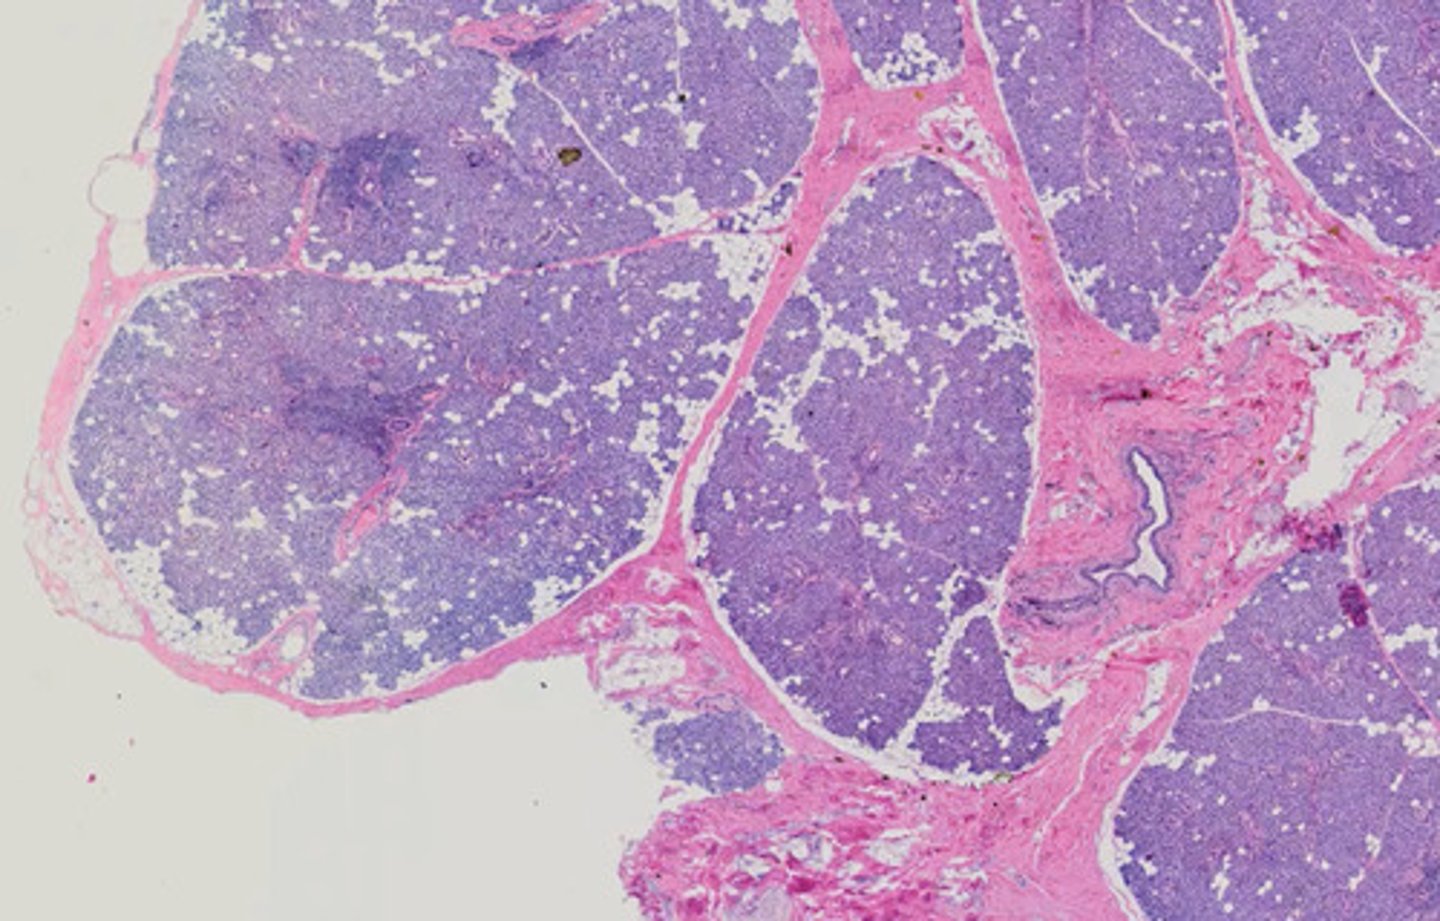

Węzeł chłonny (H+E)